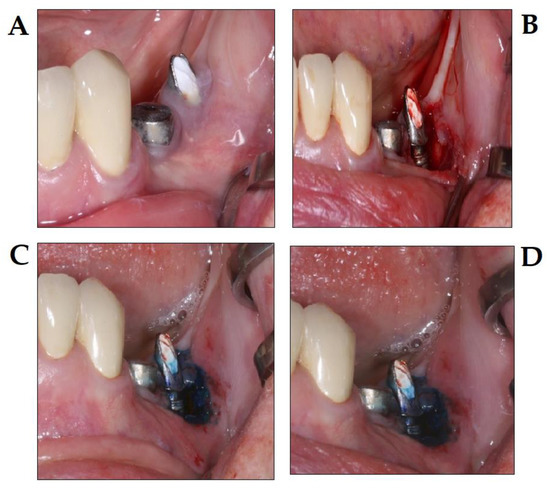

3.5. PDT in Implantology

- Khammissa, R.A.G.; Feller, L.; Meyerov, R.; Lemmer, J. Peri-implant mucositis and peri-implantitis: Bacterial infection. SADJ 2012, 67, 70, 72–74. [Google Scholar]

- Prathapachandran, J.; Suresh, N. Management of peri-implantitis. Dent. Res. J. (Isfahan) 2012, 9, 516–521. [Google Scholar] [CrossRef]

- Dörtbudak, O.; Haas, R.; Bernhart, T.; Mailath-Pokorny, G. Lethal photosensitization for decontamination of implant surfaces in the treatment of peri-implantitis. Clin. Oral Implants Res. 2001, 12, 104–108. [Google Scholar] [CrossRef]

- Sivaramakrishnan, G.; Sridharan, K. Photodynamic therapy for the treatment of peri-implant diseases: A network meta-analysis of randomized controlled trials. Photodiagnosis Photodyn. Ther. 2018, 21, 1–9. [Google Scholar] [CrossRef]